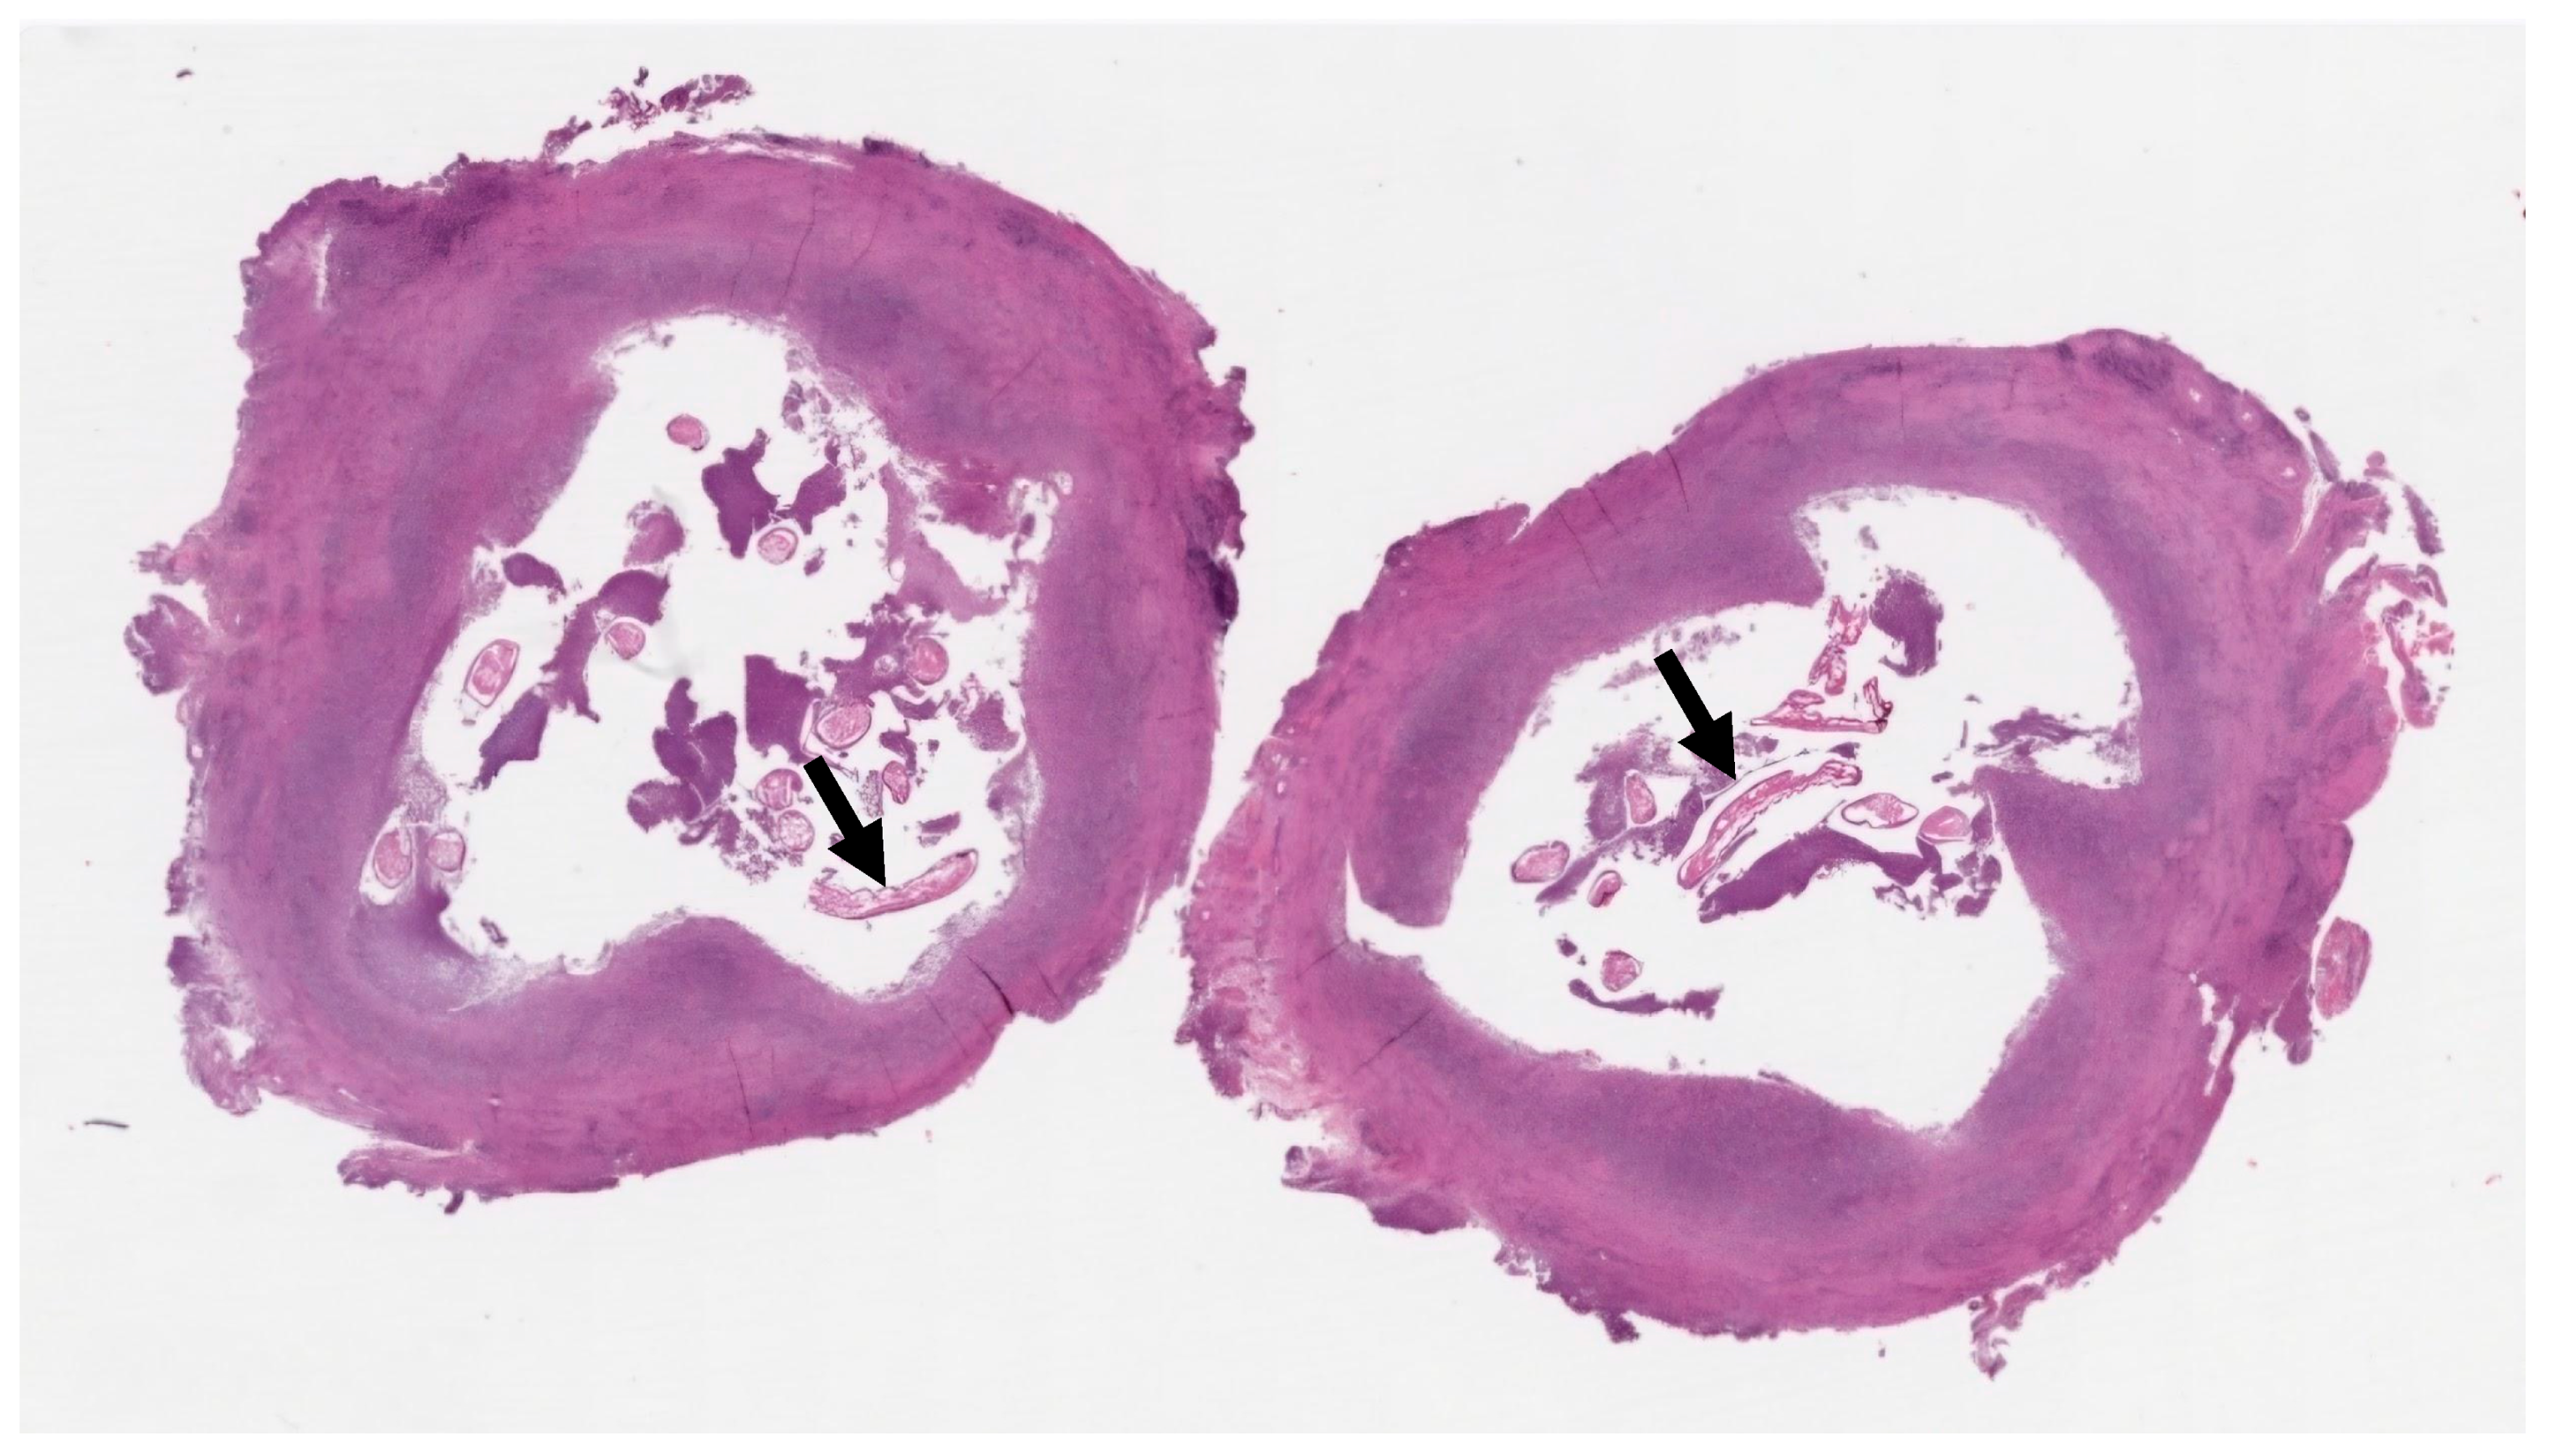

2. Case Presentation